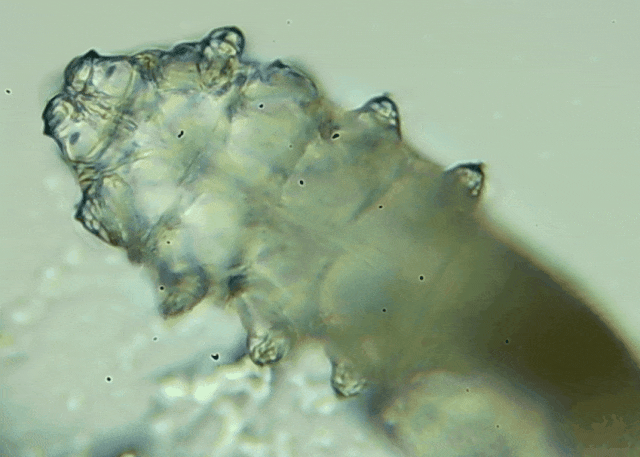

睫毛上惊现80只螨虫!【文章导读】我只是眼睛痒,结果医生说我睫毛里有80只虫?这不是恐怖片,而是真实的病例:武汉一13岁男孩,右眼9根睫毛里检出39只螨虫,左眼9根里检出47只。 而且这不是极端个案,厦门眼科中

而且这不是极端个案,厦门眼科中心干眼门诊的临床数据统计,眼睛经常红痒发炎的人群,多数都有螨虫,约80%以上的睑缘炎患者螨虫超标,一根睫毛最多能有几十只。

蠕形螨是一类肉眼看不见的寄生螨,常见的有毛囊蠕形螨和皮脂蠕形螨,常驻在人类的毛囊和皮脂腺里,尤其是眼睛的睑板腺和睫毛根部。数量少时,蠕形螨能与人体“和平共处”,但一旦你免疫力下降、油脂分泌旺盛或清洁不到位,他们就会以你难以想象的速度疯狂繁殖。